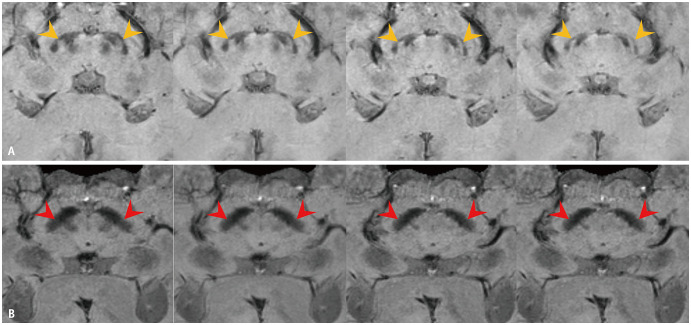

Objective: To evaluate the effect of deep learning (DL)-based artificial intelligence (AI) software on the diagnostic performance of radiologists with different experience levels in detecting nigrosome 1 (N1) abnormalities on susceptibility map-weighted imaging (SMwI).

Materials and methods: This retrospective diagnostic case-control study analyzed 139 SMwI scans of 59 patients with Parkinson's disease (PD) and 80 healthy participants. Participants were imaged using 3T MRI, and AI-generated assessments for N1 abnormalities were obtained using an AI model (version 1.0.1.0; Heuron Corporation, Seoul, Korea), which utilized YOLOX-based object detection and SparseInst segmentation models. Four radiologists (two experienced neuroradiologists and two less experienced residents) evaluated N1 abnormalities with and without AI in a crossover study design. Diagnostic performance metrics, inter-reader agreements, and reader responses to AI-generated assessments were evaluated.